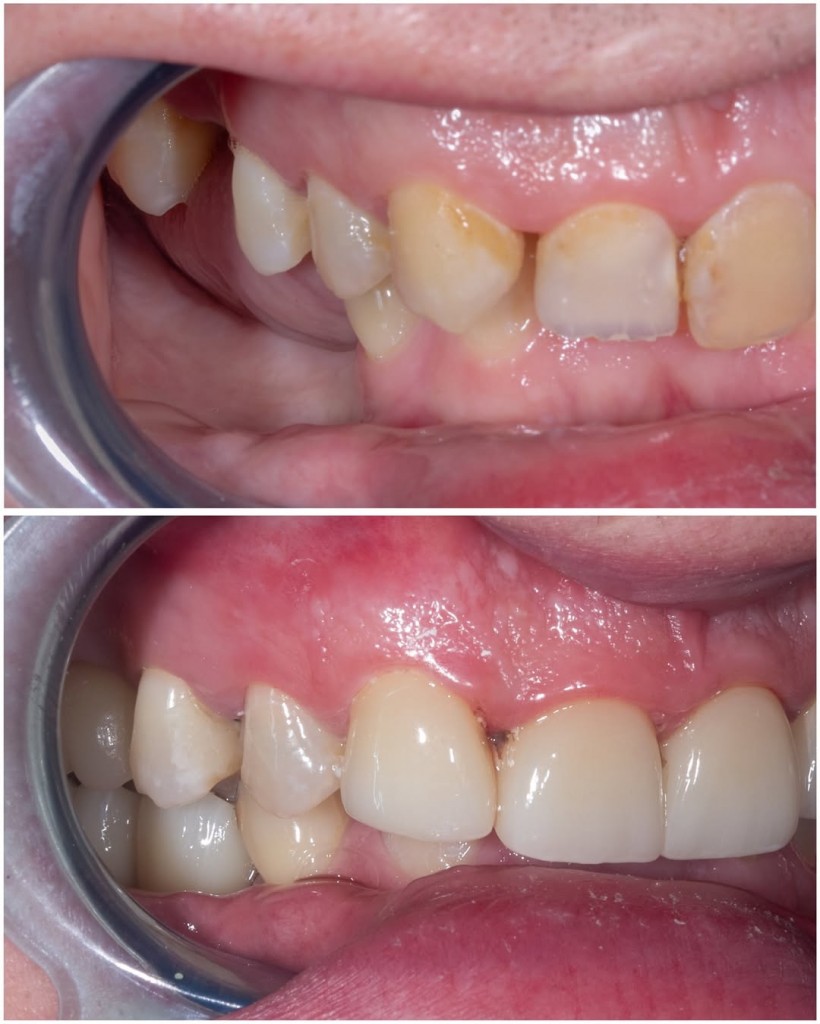

В данном клиническом случае мы показываем как можно эстетически подкорректировать врожденные аномалии. У пациента с рождения отсутствуют вторые резцы, их место заняли клыки.

Визуально мы видим несоответствие формы,  наличие промежуткав между зубами, а также дисколорит.

Было предложено исправить данный дефект с помощью коронок из диоксида циркония.

Результат понравился как пациенту, так и нам.